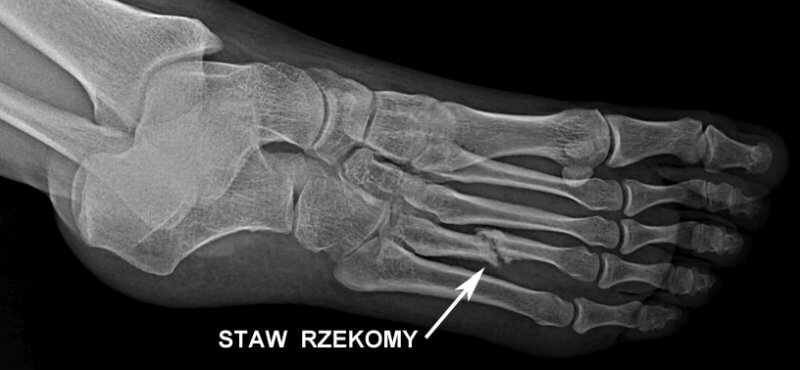

Staw rzekomy to tzw. fałszywy staw, czyli stan patologiczny, w którym dochodzi do utworzenia nienaturalnego połączenia między końcami złamanej kości, co prowadzi do ruchomości przypominającej naturalny staw. Zwykle stawy pozwalają na ruch między kośćmi i są zbudowane z chrząstki, torebki stawowej oraz innych struktur wspomagających. W przypadku stawu rzekomego, te naturalne elementy stawu są nieobecne, a ruchomość wynika z nieprawidłowego gojenia się kości.

- Kości śródręcza i śródstopia - złamania w tych obszarach również prowadzą do rozwoju stawu rzekomego, zwłaszcza gdy są nieodpowiednio stabilizowane lub w przypadku urazów złożonych.